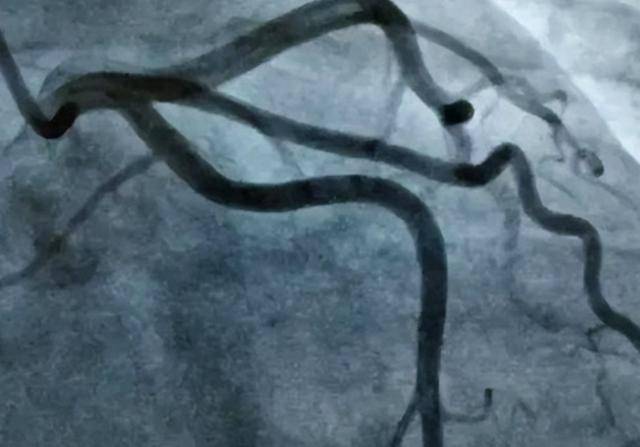

操作时通过细导管注射造影剂,借助X光“看清”血管是否狭窄或堵塞,是诊断冠心病最直接、最权威的手段。

但也正因为“有侵入性”,只有当明确存在心血管高危情况或其他筛查查不明病因时,才会被建议做冠脉造影。